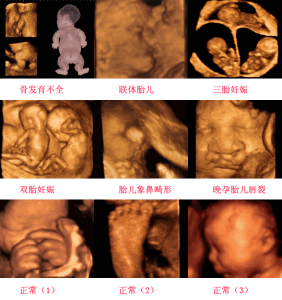

四維彩色超聲診斷儀是目前世界上最先進的彩色超聲設備。“4D”是“四維”的縮寫。4D超聲技術就是採用3D超聲圖像加上時間維度參數,能夠實時獲取三維圖像,超越了傳統超聲的限制。它提供了包括腹部、血管、小器官、產科、婦科、泌尿科、新生兒和兒科等多領域的多方面的套用。其結果是:能夠顯示您未出生的寶寶的實時動態活動圖像,或者其它人體內臟器官的實時活動圖像。四維彩超與普通彩超的區別

彩超圖像

同其它超聲診斷過程相比,可以實時的觀察人體內部器官的動態運動。臨床醫生和超聲科大夫可以檢測和發現各種異常,從血管畸形到遺傳性綜合徵。四維彩超能夠多方位、多角度地觀察宮內胎兒的生長發育情況,為早期診斷胎兒先天性體表畸形和先天性心臟疾病提供準確的科學依據。

過去的B超設備只能檢查胎兒的生理指標,而四維彩超還能對胎兒的體表進行檢查,如唇裂,脊柱裂,大腦、腎、心臟、骨骼發育不良等,以便儘早的進行治療。另外,四維彩色超聲診斷儀出色的人體工程學設計,不存在射線、光波和電磁波等方面的輻射,對人體的健康沒有任何影響。

四維彩超的好處

四維彩超不再是僅僅感覺寶寶的呼吸和運動,而是可以親眼目睹他們的一舉一動和乖巧的秀容。更為重要的是,四維彩超能夠多方位、多角度地觀察宮內胎兒的生長發育情況,為早期診斷胎兒先天性體表畸形和先天性心臟疾病提供準確的科學依據。過去的B超設備只能檢查胎兒的生理指標,而四維彩超還能對胎兒的體表進行檢查,如唇裂,脊柱裂,大腦、腎、心臟、骨骼發育不良等,以便儘早的進行治療,生個聰明健康的小寶寶。

四維彩超能進行宮內寫真,讓準媽媽看到宮內寶寶的一舉一動,親身體會到寶寶的音容笑貌!四維彩超可以把宮內四維彩超寶寶的動態刻錄成dvd作為寶寶的0歲寫真!永久留念!

四維彩超的最佳時間

做四維彩超的最佳時間是因個人而異,一般而言孕期可分為三個階段:孕前期(1月-3月),孕中期(3月-6月),孕晚期(6月-9月)。

做四維彩超的最佳時間為懷孕5-8(20-28周)個月,因為這個時段胎兒的肢體及各主要臟器已經全部發育,而且羊水較適合做胎兒畸形篩查。但因孕婦的個體差異,個人的具體時間還請和醫生聯繫,按醫囑時間定。

1.為拍胎寶寶全身:這時候可以選擇孕前期去做四維彩超,這時候胎寶寶還小,透過儀器可照出寶寶全身,值得提醒的是,1-2月不建議去做四維彩超,這個孕期做四維存在爭議。

2.為排查胎寶寶外在缺陷:這時候可以選擇孕中期或孕晚期去做四維彩超,這時候寶寶身體已經有一定的發展,照寶寶的全身已經不可能了,但可以去觀察寶寶某個部位的形態。